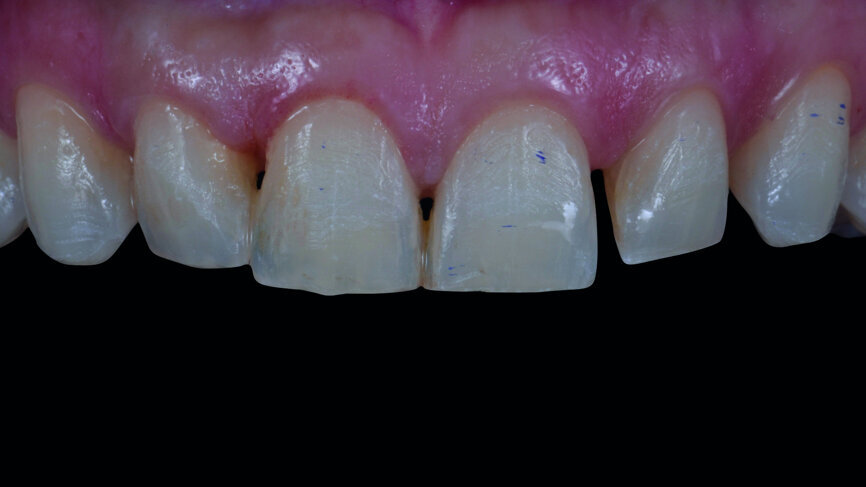

Fig. 2a: Anterior teeth after orthodontic treatment.

Fig. 2b: Extraoral photographs after orthodontic treatment.

A 35-year-old patient presented at the office with the chief desire that the aesthetics in the anterior region be changed (Fig. 1). A diagnostic wax-up was performed, followed by mock-up fabrication, in order to obtain a preliminary visualisation of the final outcome. Orthodontic treatment was proposed in order to align the teeth in a more favourable position for veneers requiring minimal preparation and to reduce the overbite. One year after treatment, the patient returned for the final prosthetic rehabilitation (Figs. 2a & b).